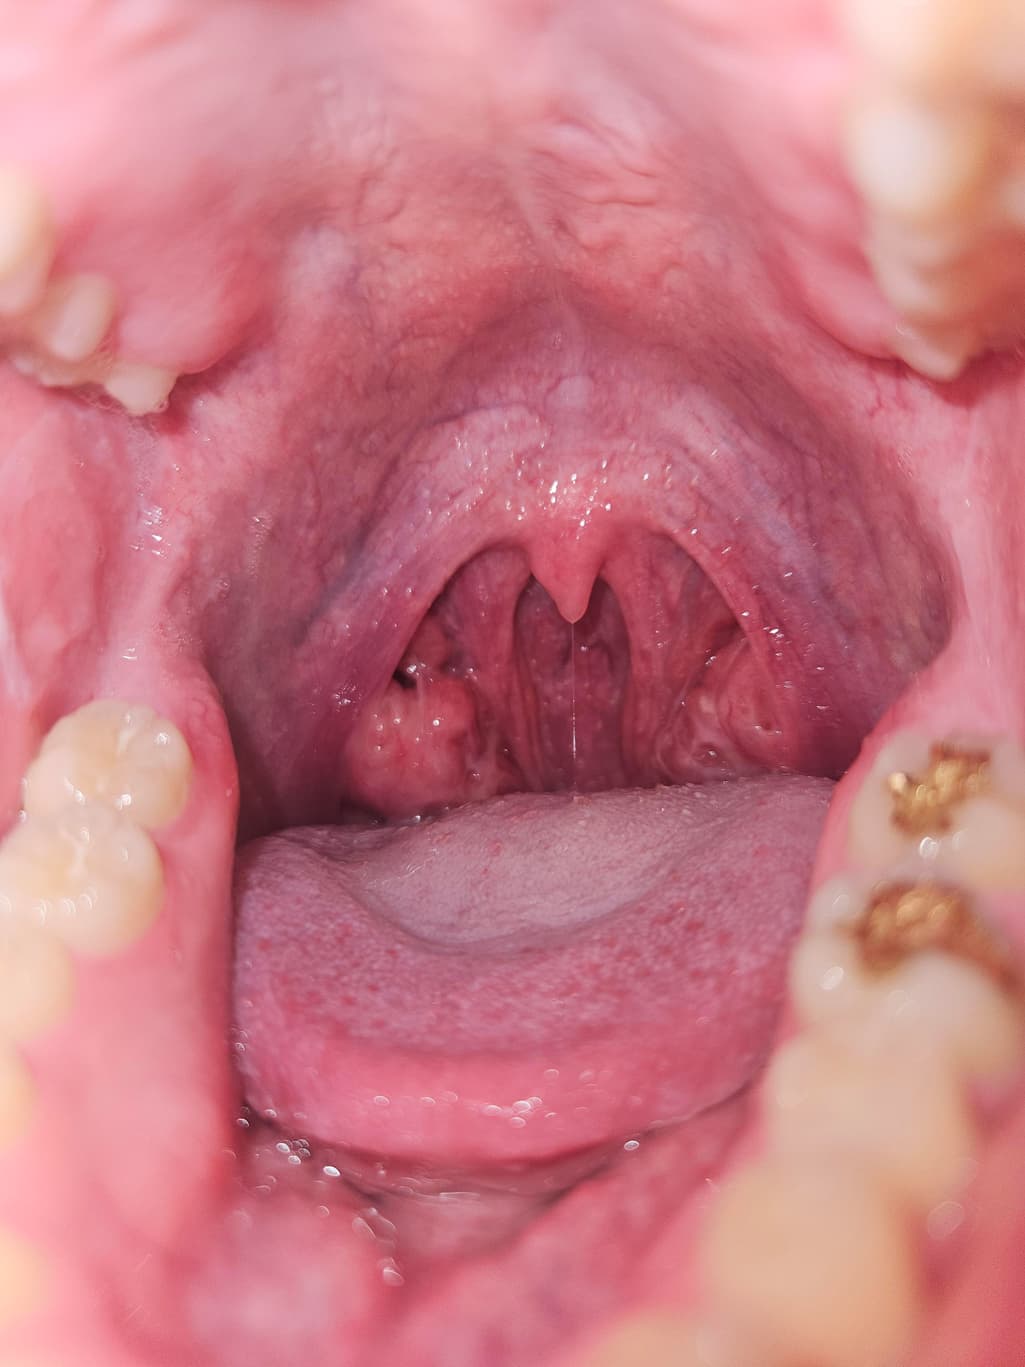

사진에서 보이듯이 오른쪽 편도에 볼록한게 보여서요, 혹시 종양일까요?

실제로 사진에 올려주신 것과 같은 비대칭적인 편도의 크기 변화는 양성 변화인 경우가 더 많습니다.

편도에는 음식물 찌꺼기, 죽은 세포 등이 쌓여 딱딱한 편도 결석이 생기기도 합니다. 이 결석은 노란색 또는 흰색의 돌처럼 보이며 냄새가 날 수 있습니다. 크기가 크면 혹처럼 보일 수도 있습니다.

편도 낭종도 드물지만 발생할 수 있으며 대부분 양성입니다. 특별한 증상이 없으면 큰 문제는 아닙니다.

어릴 때부터 편도가 크다는 설명을 들었다면 선천적으로 편도가 비대칭적으로 큰 것일 수도 있겠습니다.

20대의 젊은 연령에서는 편도암이 매우 드물지만, 편도 혹의 크기가 변화하거나, 통증, 출혈, 궤양, 목에 임파선이 만져지는 증상이 동반되면 반드시 이비인후과 전문의 진료를 통해 조직검사를 진행해야 합니다.

사진만으로는 정확한 진단이 어렵기 때문에, 조직검사 등 추가 검사가 필요할 수 있습니다.